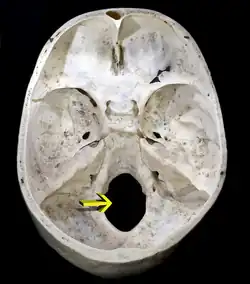

Большое затылочное отверстие в черепе человека, вид сверху | |

Большое затылочное отверстие (лат. Foramen occipitale magnum) — овальное отверстие в затылочной кости черепа, посредством которого черепная полость сообщается с позвоночным каналом. В районе большого затылочного отверстия происходит переход продолговатого мозга в спинной[1]. Правый и левый затылочные мыщелки образуют сочленения с 1-м шейным позвонком. Через это отверстие, самое большое в черепе человека, проходят не только продолговатый мозг, но и корешок добавочного нерва, мозговые оболочки, кортиева мембрана, крыловидные связки и такие элементы кровеносной системы как передняя и задняя спинномозговые артерии и позвоночная артерия[2].

Большое затылочное отверстие ограничено затылочной чешуёй сзади, базилярной частью затылочной кости спереди и соединяющими эти две части затылочной кости затылочными мыщелками (латеральными частями) справа и слева[1][3]. Положение большого затылочного отверстия различается от вида к виду. Так, у человека оно сдвинуто вперёд по сравнению с современными человекообразными обезьянами (в частности, шимпанзе), что соответствует осанке, сформировавшейся в результате прямохождения. Положение большого затылочного отверстия используется палеонтологами для определения того, относить ли тот или иной род ископаемых приматов к гоминидам[4]. В то же время для других двуногих млекопитающих положение большого затылочного отверстия может определяться иными факторами — например, в случае мешотчатых прыгунов и тушканчиковых, увеличившимися в результате эволюции слуховыми буллами[5].